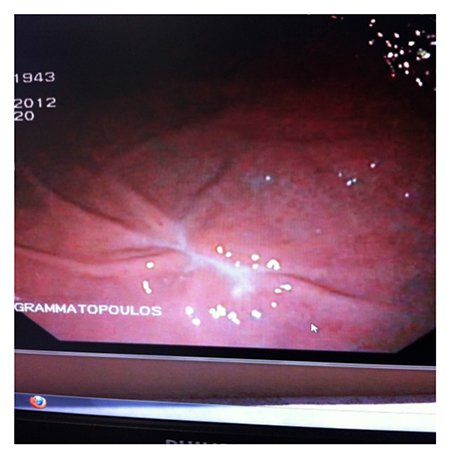

Peroral endoscopic myotomy (POEM) for esophageal achalasia has started being performed in Greece in the last two years, exclusively at Metropolitan Hospital, with successful results. The procedure is performed from the mouth with the help of an endoscope, at the Hospital's Endoscopy Department. A special lancet is fitted to the endoscope and with precise movements, it cuts the contracted circular muscle fibers in the lower third of the esophagus which are responsible for causing achalasia.

Conventional treatment methods include: endoscopic balloon dilation (but with temporary results, high failure rates and frequent revision procedures) and Heller myotomy, which is performed in very severe cases, has high failure rates and is accompanied by an antireflux procedure. The revolutionary peroral endoscopic myotomy (POEM) is the most contemporary, minimally invasive technique for radical treatment of all types of esophageal achalasia.